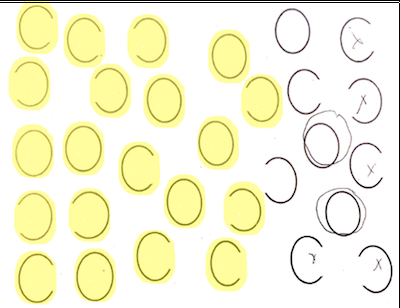

A series of 256 consenting acute stroke patients (82 LH and 174 RH) completed a neglect task with 30 ovals – 10 full, 10 with a gap on the left, and 10 with a gap on the right. Patients were asked to circle full ovals and cross out ovals with a gap on either side. We defined VCN as >10% of ovals unmarked after the most extreme mark (Fig. 2), and SCN as neglecting or incorrectly marking >10% of contralesional gaps (Fig. 3). On FLAIR sequences, we identified FHVs in 4 MCA regions: frontal, temporal, parietal, and insular, as well as ACA and PCA territories. Each region was scored from 0 to 2: 0 = no FHVs; 1 = 1-2 FHVs on 1-2 slices; 2 = 3 or more vessels on 1 slice or 3 or more slices with at least 1 FHV (total=0-12). Infarct volume was calculated after manual tracing of lesions on DWI. We used multivariable logistic regression, with the presence of VCN or SCN as the dependent variable, and FHV ratings in each territory, infarct volume, and age as independent variables. We used chi squared tests to test associations between dichotomous variables.